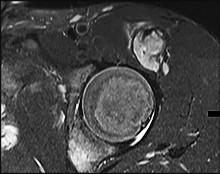

This patient has a dedifferentiated liposarcoma within a preexisting atypical lipomatous tumor. The imaging demonstrates a large fatty mass with increased internal septations proximally (the atypical lipomatous tumor) and a solid enhancing mass distally (the dedifferentiated portion). A biopsy reveals a high-grade liposarcoma. The other diagnostic responses do not reflect sarcomatous transformation of the lesion.

Surgical treatment of a high-grade sarcoma involves wide surgical resection. Radiation decreases local recurrence but does not clearly influence overall survival. The role of chemotherapy in high-grade soft-tissue sarcomas remains investigational; there is a modest (8%-15%) associated improvement in overall survival.

Intramuscular lipomas and atypical lipomatous tumors are treated with marginal resection alone. Radiation therapy for soft-tissue sarcomas may be given before or after surgery. When administered before surgery, patients have a higher wound complication rate but better long-term function attributable to lower rates of lymphedema, fibrosis, and contractures.